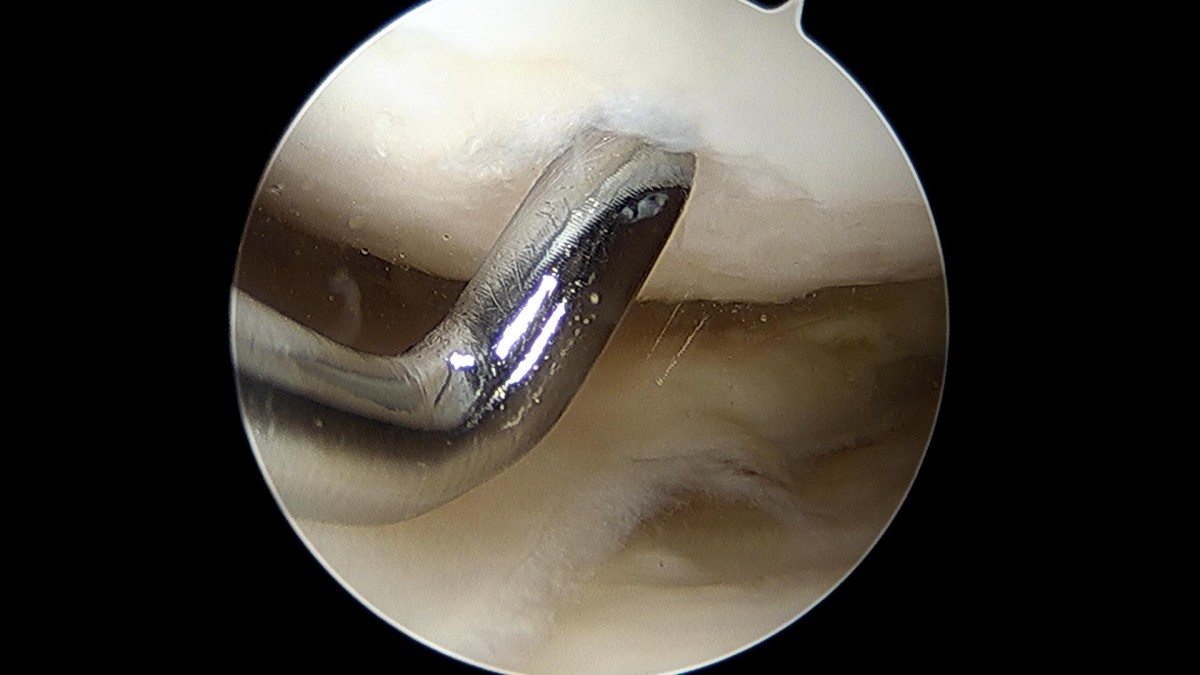

배우한원장님 무릎 경골 교정술 및 반월상 연골판 절제술 (1779)정미O 환자